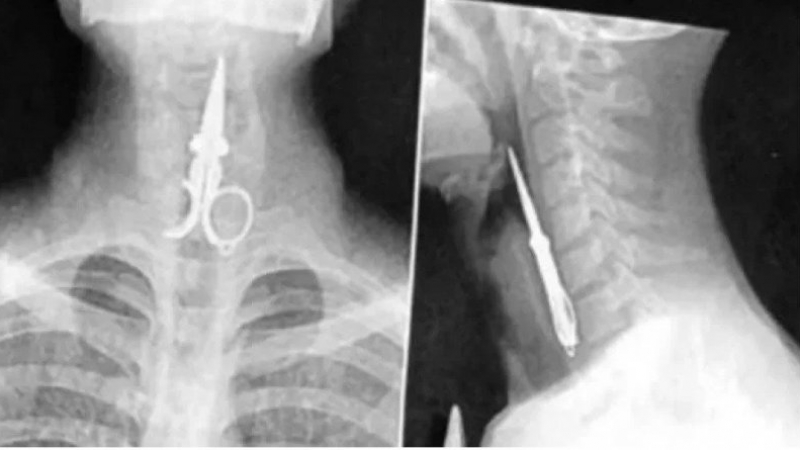

Un impensado episodio ocurrió en una cárcel de San Juan, donde un preso se tragó la mitad de una tijera como “un acto de protesta”. Se trata de Axel Hernán Rojas, que cumple condena desde 2019 por delitos contra la propiedad y ya fue protagonista de otros hechos similares en el pasado.

El suceso tuvo lugar el lunes por la noche en el penal de Chimbas, cuando Rojas, de manera deliberada, ingirió el objeto metálico. Ante la gravedad de la situación, personal penitenciario intervino rápidamente y, tras recibir la autorización del Juzgado de Ejecución Penal a cargo de Federico Zapata, dispuso su traslado a un hospital para una revisión médica.

A pesar de que el recluso se negó a recibir atención, los profesionales evaluaron su estado y determinaron que no era necesaria una intervención quirúrgica, ya que pudo expulsar la tijera por sus propios medios. Actualmente, se encuentra fuera de peligro y regresó a la cárcel.